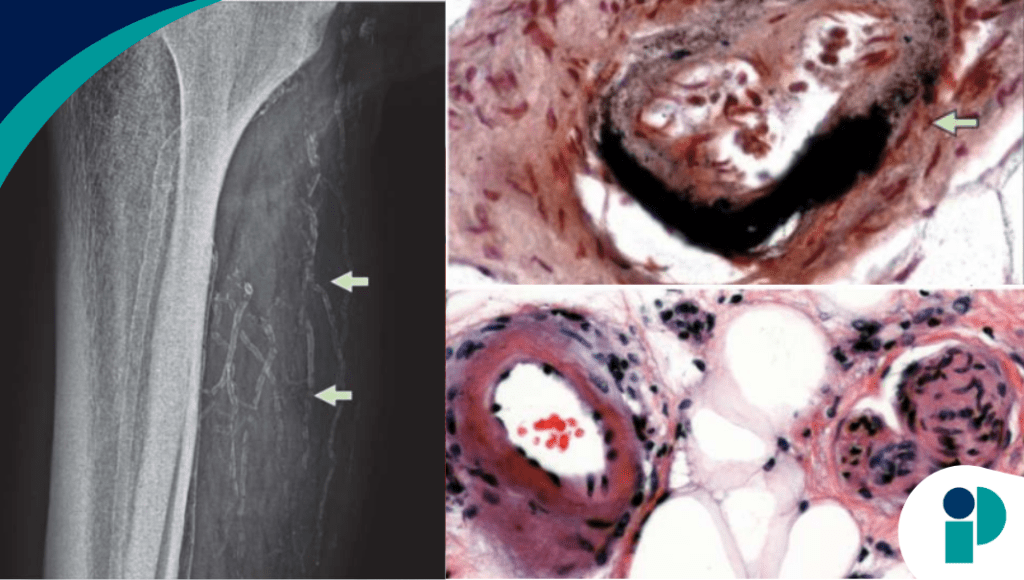

Al paciente se le realizaron diversos exámenes, entre ellos una radiografía de tejidos blandos, la cual reveló arteriolas calcificadas difusas en un patrón reticular. El examen histológico de la biopsia cutánea mostró esclerosis y trombosis de los vasos sanguíneos y la tinción de von Kossa fue positiva para depósitos de calcio, lo que confirmó el diagnóstico de calcifilaxis .